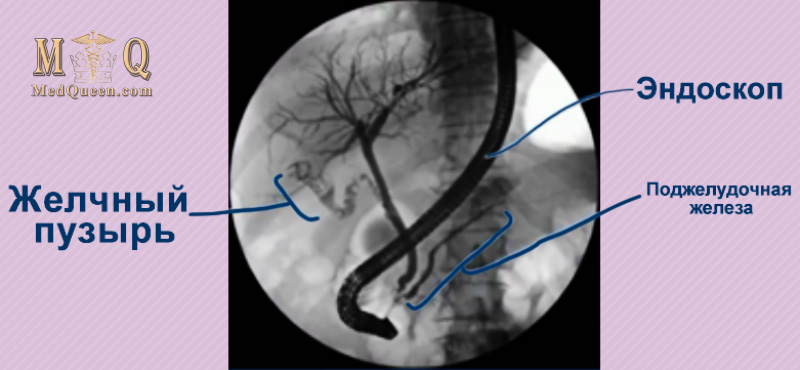

Ретроградная холангиопанкреатография (ERCP – Endoscopic retrograde cholangiopancreatography)